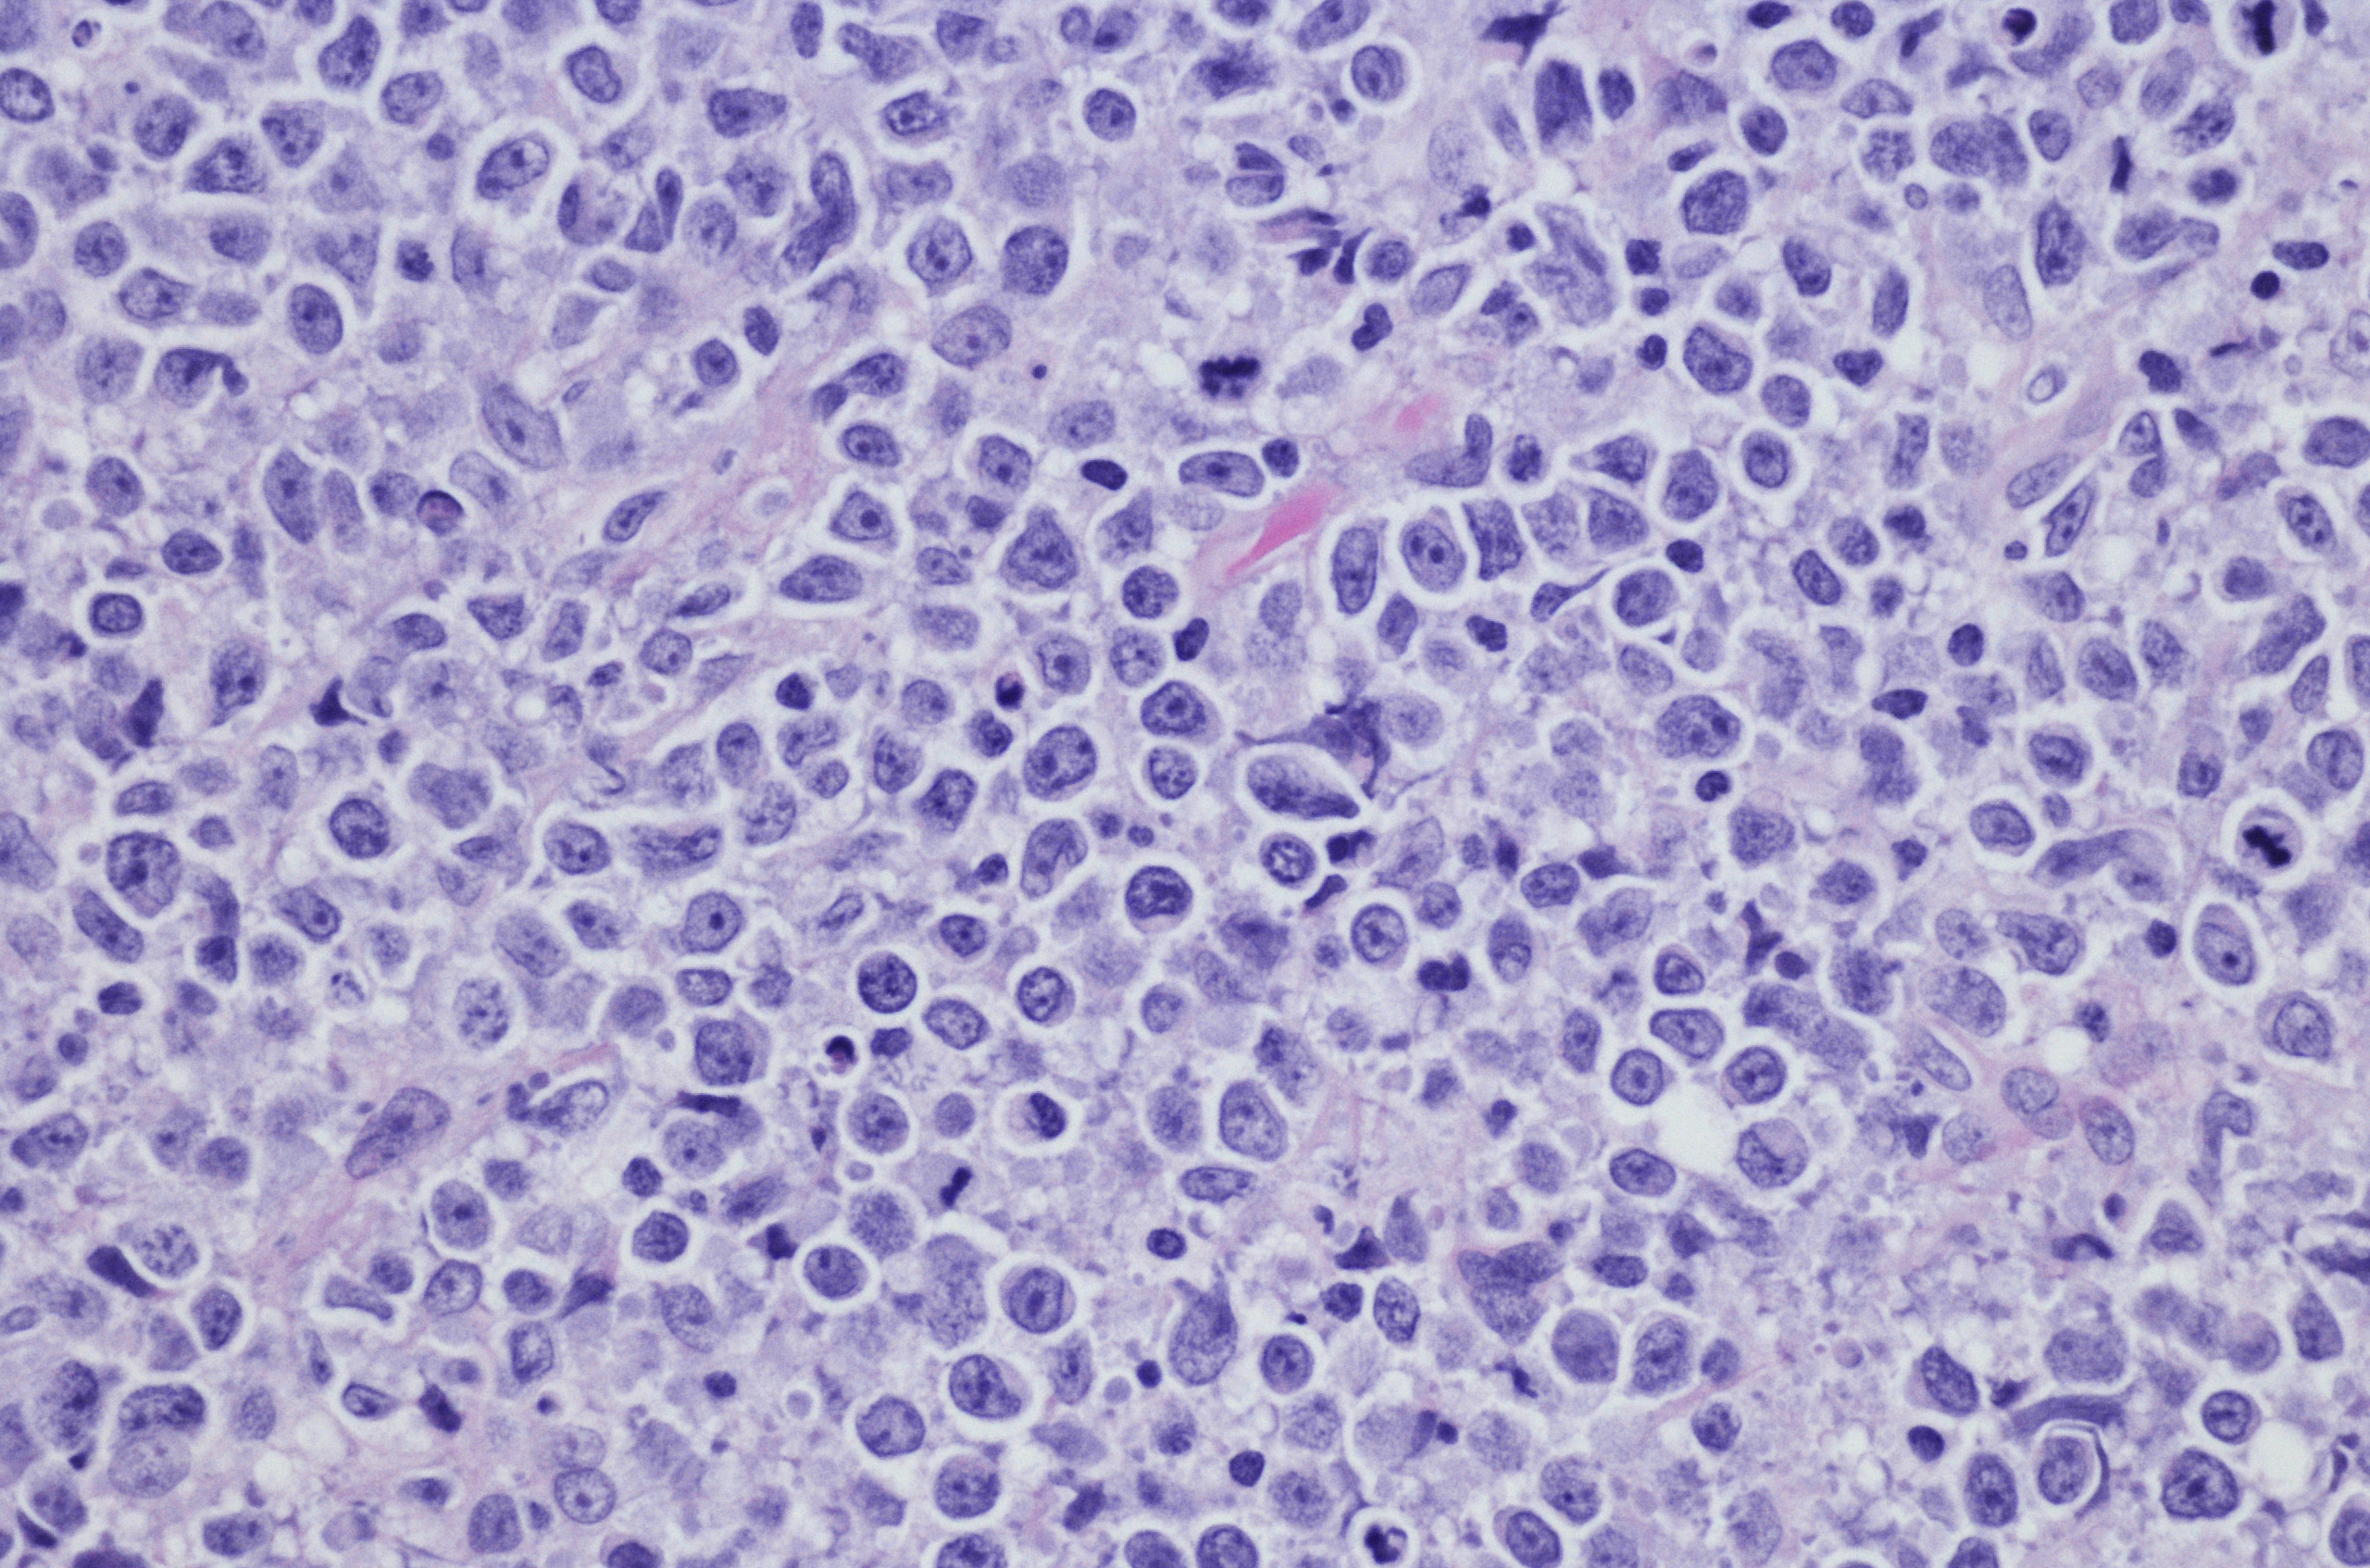

Lymphomas are most often classified by how the cancer cells look under the microscope. There are three main features of lymphoma:

Nearly all Non-Hodgkin Lymphomas belong to one of 3 main types:

All three types grow quickly and are scattered, but it is important to distinguish among them because they are treated differently.